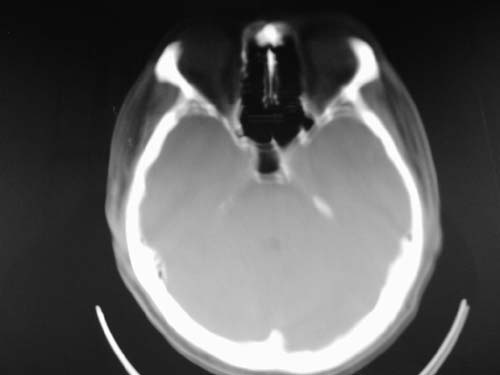

标题: CT17020:是硬膜下的吗?

脑中线内血肿,是硬膜下的吗?

硬膜下血肿,有颅骨骨折

支持镰旁硬膜下血肿,颅骨骨折,头皮损伤.

这个病人年龄不小吧,右侧脑沟不清,中线结构稍有左移,右侧额颞顶及右镰旁硬膜下血肿,另有蛛血,骨折。

外伤后引起的颅骨骨折、硬膜下血肿、皮下血肿,颅骨骨折引起的矢状窦破裂,形成大脑纵裂内血肿。